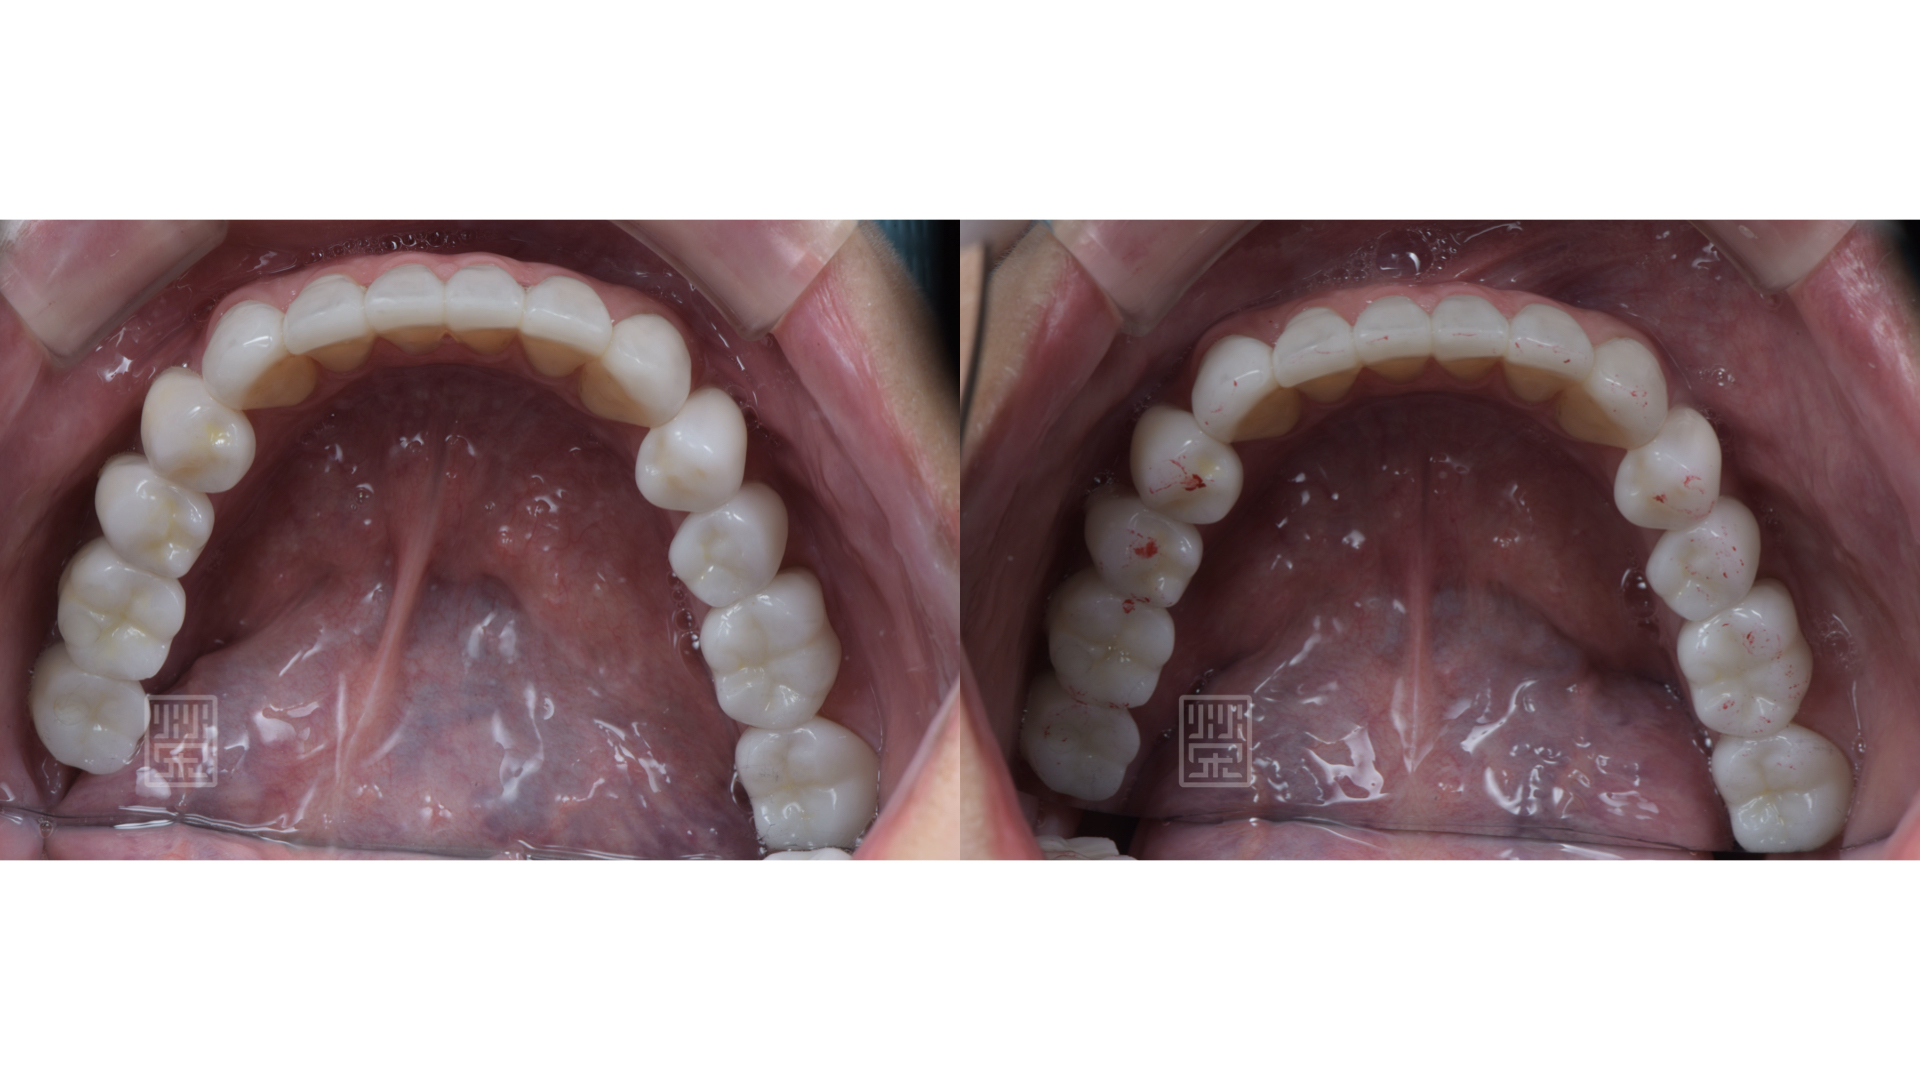

適當分配牙齒導引位置,保護前後牙

適當的咬合分配